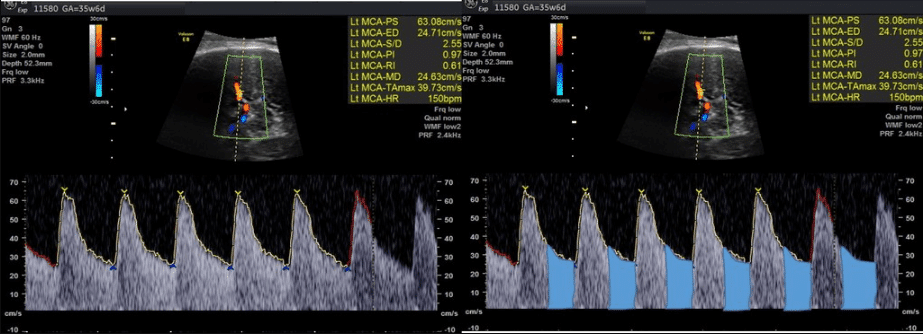

Artéria cerebral média (ACM)

Utiliza-se o Doppler da artéria cerebral média para avaliar a resposta fetal à hipóxia crônica causada por insuficiência placentária. Nessa condição, ocorre uma redistribuição do fluxo sanguíneo para órgãos vitais, como cérebro, coração e glândulas adrenais, fenômeno conhecido como centralização fetal.

Portanto, no Doppler, observa-se aumento do fluxo diastólico e redução da resistência na artéria cerebral média, sendo considerados alterados os valores de IP abaixo do percentil 5 para a idade gestacional.